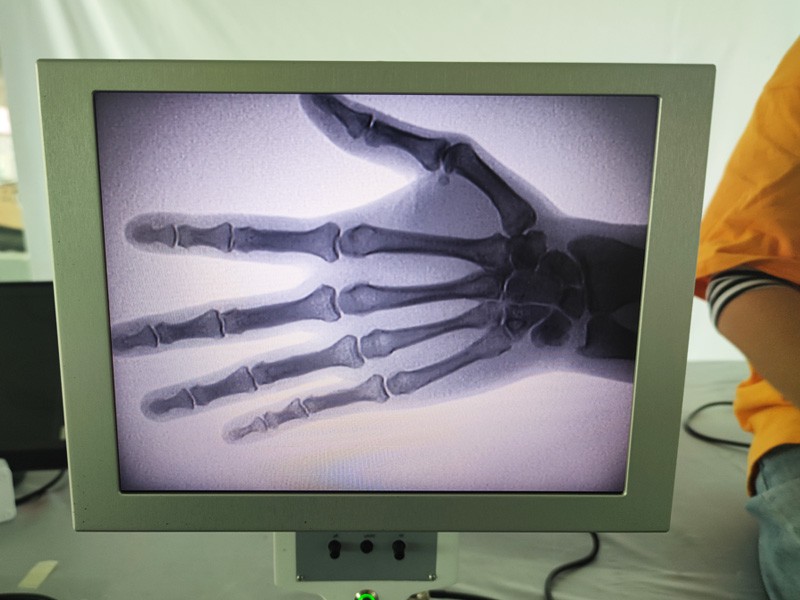

Is ionstraim iniompartha é meaisín X-gha iniompartha As-c200 le dáileog radaíochta beag agus an-sábháilte. Tá sé oiriúnach go háirithe d'aonaid agus do dhaoine aonair nach bhfuil dóthain buiséid acu agus riachtanais íseal le haghaidh pictiúr. Tá an ghlúin nua feistithe le scáileán mór 10 orlach ard-sainmhínithe, a bhfuil raon peirspictíochta níos mó aige agus is féidir leis an pailme iomlán a dhearcadh go hiomlán. Tá sé oiriúnach den chuid is mó le haghaidh peirspictíocht ortaipéideach leighis. Is féidir é a nascadh le printéir scannáin chun scannáin ortaipéideacha a phriontáil, agus is féidir é a úsáid freisin i dtáirgeadh agus i dtástáil tionsclaíoch. Gan seomra dorcha, peirspictíocht dhíreach, breathnóireacht ar an toirt, íomháú ardtaifeach agus soiléir.

Is táirge ardchaighdeáin é ár Meaisín X-gha Ortaipéideach a dearadh go háirithe le haghaidh íomháithe ortaipéideacha. Is féidir é a úsáid le haghaidh diagnóis agus pleanáil cóireála ar choinníollacha ortaipéideacha éagsúla, lena n-áirítear bristeacha, dislocations, airtríteas, agus siadaí cnámh. Tá sé feistithe le teicneolaíocht X-gha chun cinn a chuireann ar chumas íomhánna ardcháilíochta le nochtadh radaíochta laghdaithe. Tá córas íomháithe ardtaifigh ag an meaisín agus is féidir íomhánna d'aon struchtúr cnámh a ghabháil le soiléireacht mhór.

1. Teicneolaíocht íomháithe chun cinn: Úsáideann ár Meaisín X-gha Ortaipéideach teicneolaíocht íomháithe chun cinn chun íomhánna ardchaighdeáin de chnámha agus hailt a ghabháil, ag soláthar diagnóis chruinn agus torthaí cóireála feabhsaithe.

3. Taispeántas íomhá mór: Tá taispeáint íomhá mór ag an meaisín, ag soláthar sreabhadh oibre éifeachtach agus aithint éasca ar thorthaí criticiúla.